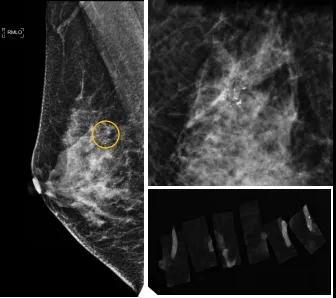

46歲的某女士在西安國(guó)際醫(yī)學(xué)中心醫(yī)院體檢時(shí),行乳腺X線攝影(俗稱(chēng)鉬靶)發(fā)現(xiàn)右乳可疑簇狀鈣化,分布范圍不到1厘米,臨床觸不到,超聲很難發(fā)現(xiàn),但是這種鈣化風(fēng)險(xiǎn)比較高,依據(jù)國(guó)際BI-RADS指南需要明確病理!

西安國(guó)際醫(yī)學(xué)中心醫(yī)院影像診療中心陳寶瑩副主任帶領(lǐng)的團(tuán)隊(duì),采用全數(shù)字化乳腺X線三維立體定位系統(tǒng)可實(shí)施。這個(gè)團(tuán)隊(duì)的成員大部分來(lái)自知名三甲醫(yī)院,有著十余年影像引導(dǎo)下乳腺介入診療的經(jīng)驗(yàn),X線引導(dǎo)穿刺定位和活檢例數(shù)居西北前列。為減少患者創(chuàng)傷,在詳細(xì)判讀了患者資料,并與患者及甲乳外科劉曉敏主任充分溝通的基礎(chǔ)上,團(tuán)隊(duì)確定采用全數(shù)字化乳腺X線三維立體定位系統(tǒng)下實(shí)施粗針活檢。

當(dāng)天,乳腺X線三維立體定位系統(tǒng)清晰顯示出了所有鈣化。為了獲取充足的組織量,保證病理診斷的準(zhǔn)確性,團(tuán)隊(duì)選用14G穿刺針并多點(diǎn)、多角度取材,組織取出后,又立即在高清標(biāo)本攝影系統(tǒng)中進(jìn)行投照,從而確定了取出組織中具有足夠的可疑鈣化。整個(gè)過(guò)程患者無(wú)任何不適,活檢結(jié)束后即回家觀察。